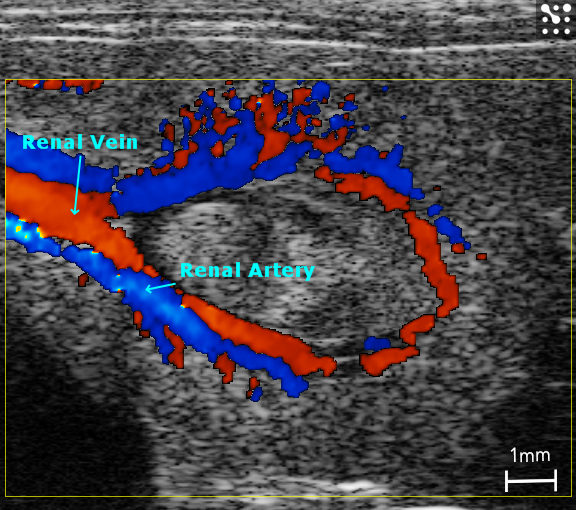

Measuring the velocity of blood flow is crucial to understanding disease states. Pulsed wave (PW) Doppler uses the Doppler principle that moving objects change the characteristic of sound waves. By sending short and quick pulses of sound, it becomes possible to accurately measure the velocity of blood in a precise location and in real time.

Using Color Doppler Mode, flow velocities within vessels are color-coded. The intensity of the color is a function of velocity. Flow towards and away from the transducer is indicated either as red or blue, respectively.

Color Doppler - Renal vein/artery